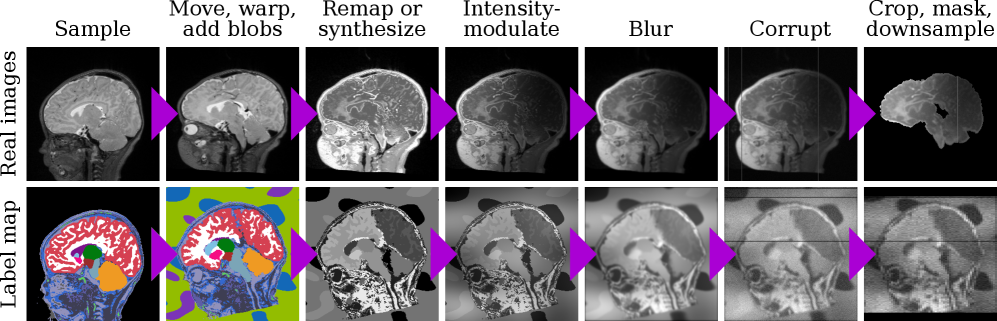

Refer to caption

Figure 1: BabySeg framework. At every step, we sample images and a label map from a subject. First, we randomly move and deform these inputs, adding synthetic background structures to the label map. Second, we synthesize training images and apply a series of corruptions. Third, the BabySeg U-Net predicts a single segmentation map from these inputs.

Figure 5: Data engine. First, we sample, move, and warp images and the associated label map, adding synthetic background blobs to the latter. Second, we remap intensities and generate images from the label map. Third, we apply a series of corruptions, to obtain images for training. All steps are randomized.